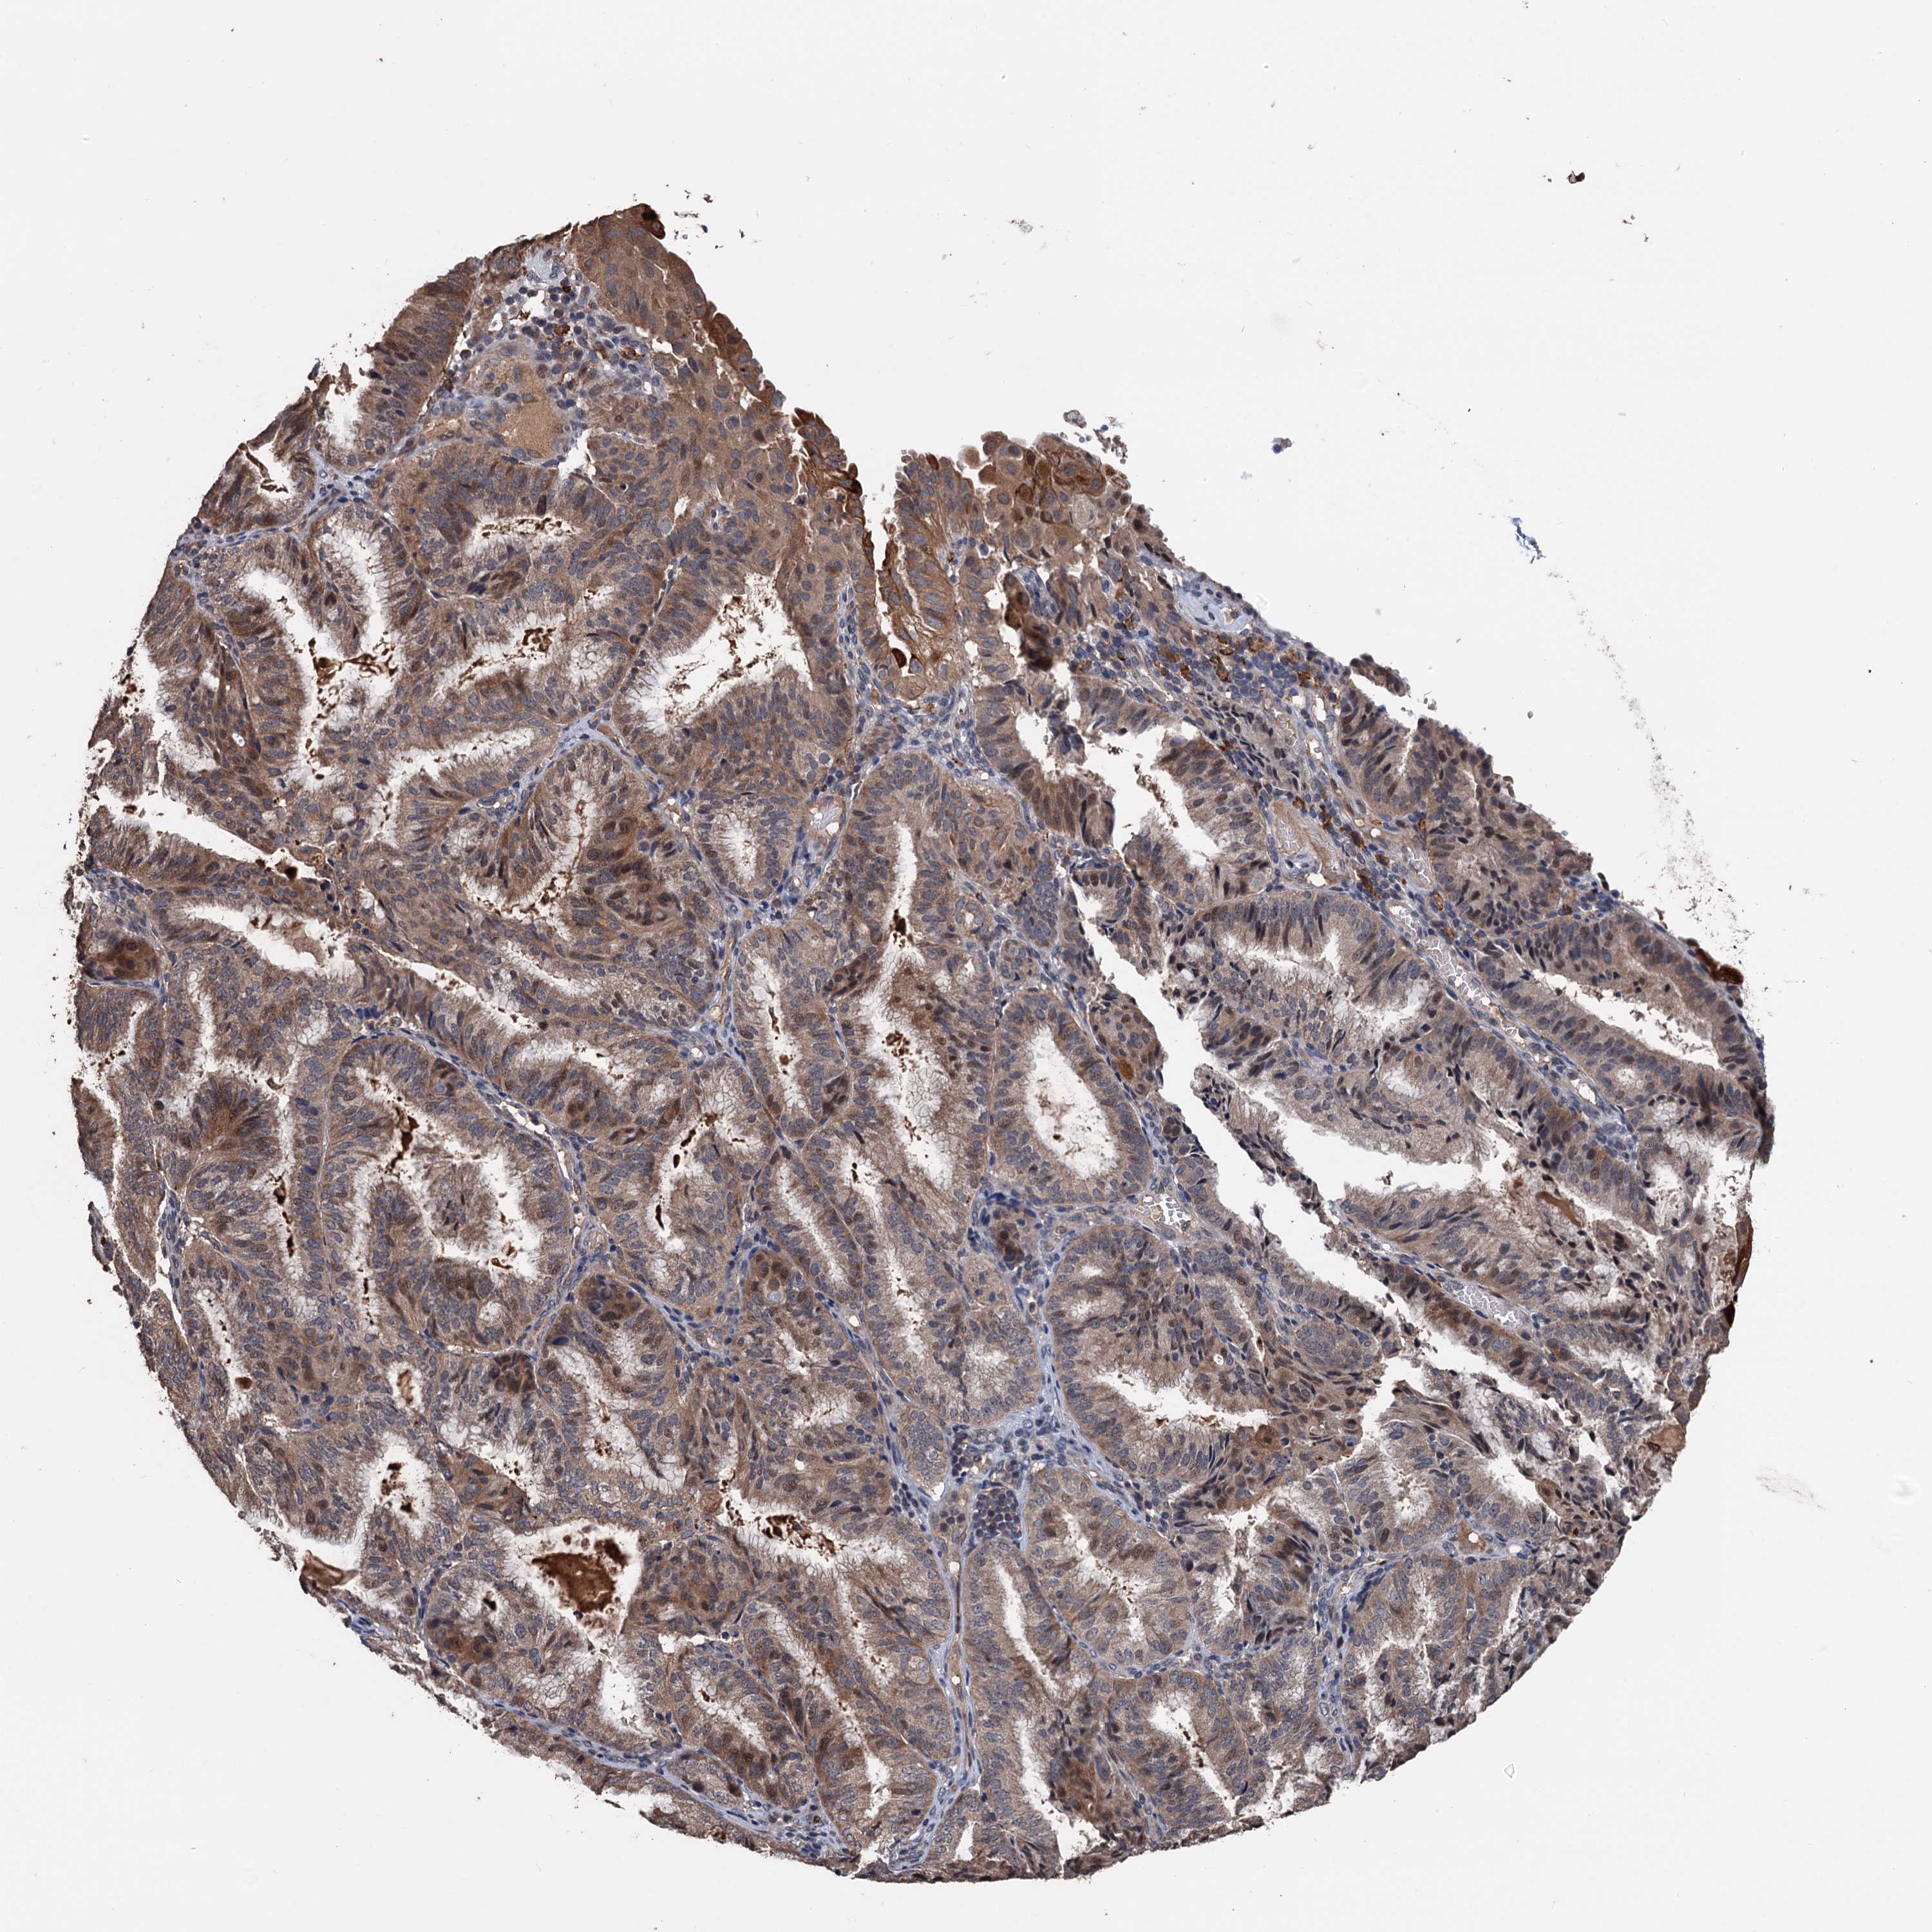

ENDOMETRIAL CANCER - Protein expressioni

A mouse-over function shows sample information and annotation data. Click on an image to view it in a full screen mode. Samples can be filtered based on level of antibody staining by selecting one or several of the following categories: high, medium, low and not detected. The assay and annotation is described here.

Note that samples used for immunohistochemistry by the Human Protein Atlas do not correspond to samples in the TCGA dataset.

Antibody stainingi

Antibody staining in the annotated cell types in the current human tissue is reported as not detected, low, medium, or high, based on conventional immunohistochemistry profiling in selected tissues. This score is based on the combination of the staining intensity and fraction of stained cells.

Each image is clickable and will lead to virtual microscopy that enables deeper exploration of all samples and also displays staining intensity scores, fraction scores and subcellular localization as well as patient and tissue information for each sample.

Antibody HPA039843

Staining

High

Medium

Low

Not detected

Intensity

Strong

Moderate

Weak

Negative

Quantity

>75%

75%-25%

<25%

None

Location

Nuclear

Cytoplasmic/membranous

Cytoplasmic/membranous,nuclear

Adenocarcinoma, NOS